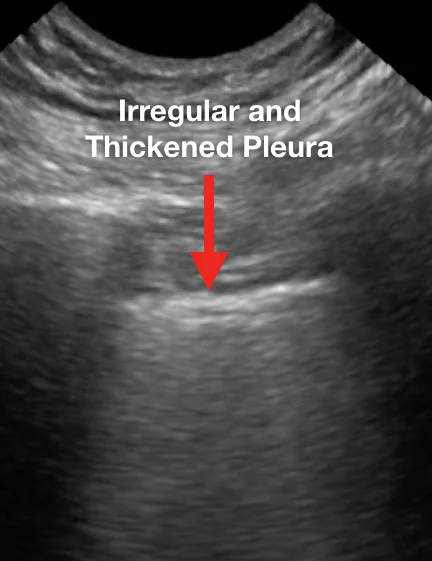

Характерные выводы включают следующее:

Наблюдаемые паттерны происходили в промежутке от легкого альвеолярного интерстициального паттерна до тяжелого двустороннего интерстициального паттерна и консолидации легких. В таблице 1 приведены типичные результаты УЗИ легких у пациентов с респираторным заболеванием COVID-19 в сравнении с данными КТ грудной клетки.

Ниже представлен ряд изображений патологических изменений, которые Вы можете увидеть при УЗИ легких пациентов с COVID-19. Эти изменения можно найти в любой части легкого, поскольку COVID-19 имеет мультифокальное распределение. Возможно сочетание областей нормального легкого и области с патологией. Патологические изменения легких могут отсутствовать в начале заболевания и при легком течении COVID-19, однако, по мере его прогрессирования, Вы можете наблюдать всё больше патологических изменений.

Ниже приведены примеры УЗ-картины легких пациентов с COVID-19.